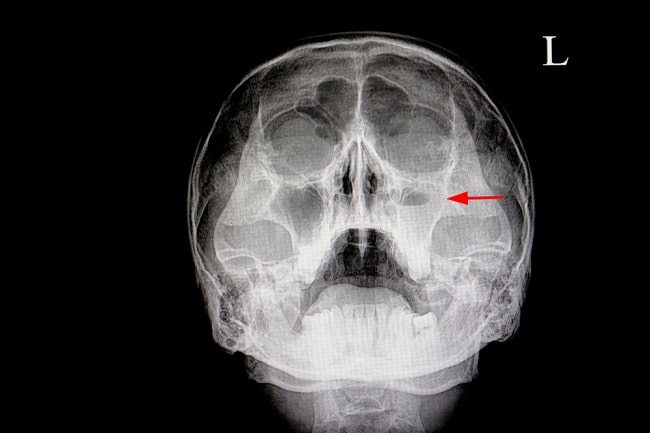

Hasil rontgen Kepala Korban

Di lansir dari VIVA.co.id Hasil rontgen menunjukkan, JJ mengalami trauma kranium akibat retak halus pada bagian kepala. "Memang dianjurkan untuk CT Scan wajah lagi," kata tenaga medis yang periksa korban.

Dalam surat keterangan hasil pemeriksaan radiologi, tertulis beberapa keterangan medis terdapat suspek garis faktur hairline di Os Zygoma kiri dengan penebalan jaringan di sekitarnya.

Sehingga dokter bedah menyarankan anak korban diperiksa lagi dengan CT Scan wajah rekonstruksi 3D non kontras. "Kami tadi bawa hasil rontgennya. Kami besok harus ke rumah sakit lagi. Tadi ada kasih obat dari dokter untuk obat pusing," tutup Kampianus.